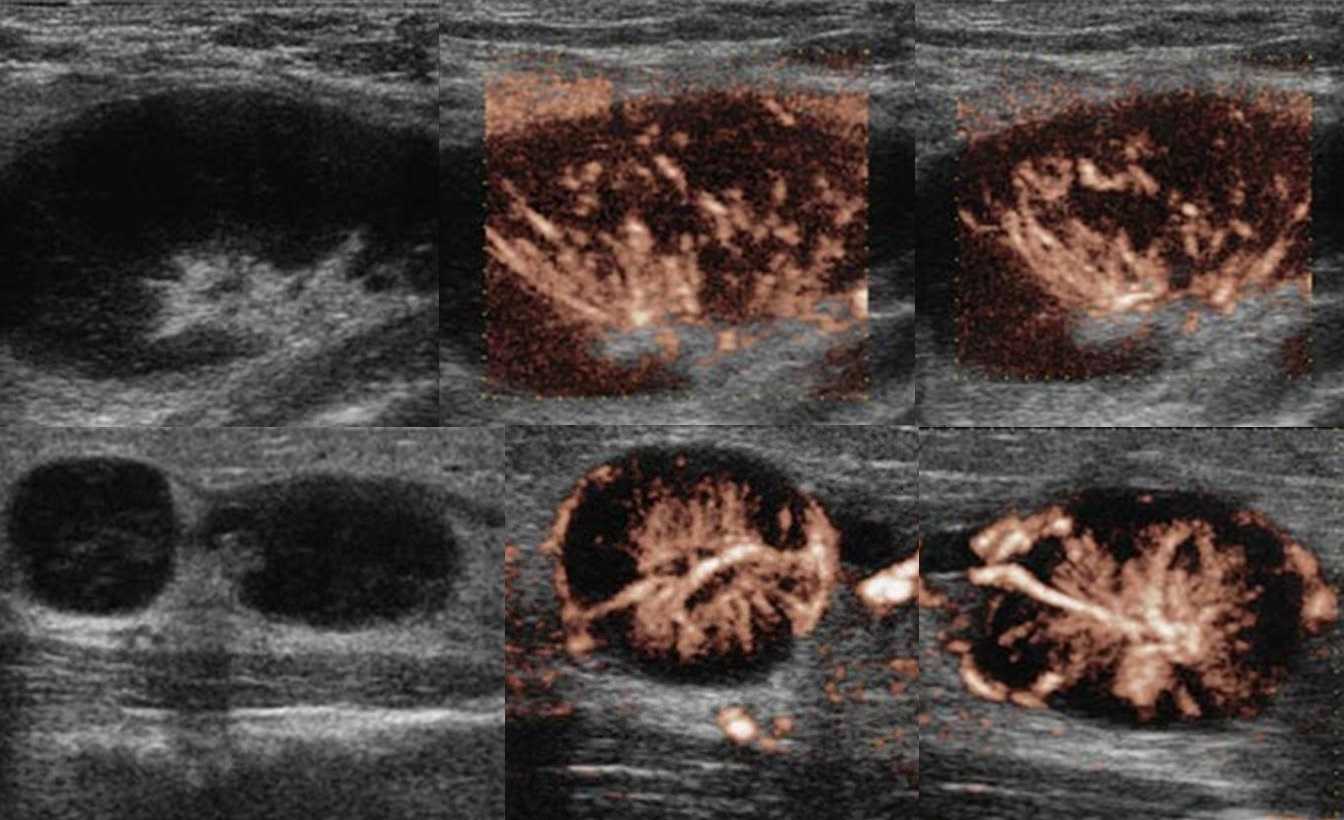

Туберкулез чаще поражает лимфоузлы шеи, подмышечной и паховой области. Обычно туберкулезный лимфаденит развивается медленно, лимфоузлы безболезненные, средний размер 3 см, но иногда могут достигать 10 см. На УЗИ пораженные лимфоузлы увеличены, гипоэхогенные, с нечетким контуром, часто можно увидеть выраженный периаденит и спаянные пакеты лимфоузлов. Для туберкулезного лимфаденита характерна неоднородная эхоструктура — анэхогенные кистозные полости и кальцинаты. При прогрессировании заболевания может образоваться абсцесс и свищи.

Рисунок. На УЗИ на шее определяется группа увеличенных лимфоузлов, неправильной формы; эхогенность понижена, центральный рубчик отсутствует; неоднородные за счет анэхогенных аваскулярных зон — очаги некроза; кровоток усилен, ход сосудов неправильный, выраженный подкапсульный кровоток. Заключение по результатам биопсии: Туберкулез лимфоузлов.

Рисунок. На УЗИ увеличенные лимфоузлы, неправильной формы с размытыми границами; эхогенность пониженная, центральный рубчик отсутствует; неоднородные за счет мелких кистозных полостей и гиперэхогенных включений с акустической тенью позади (кальцинаты). Заключение по результатам биопсии: Поражение лимфоузлов атипичными микобактериями. Гистологически очаги инфекции М. tuberculosis и атипичных микобактерий часто неразличимы. Классическим морфологическим проявлением в обоих случаях служит гранулема с казеозным некрозом.